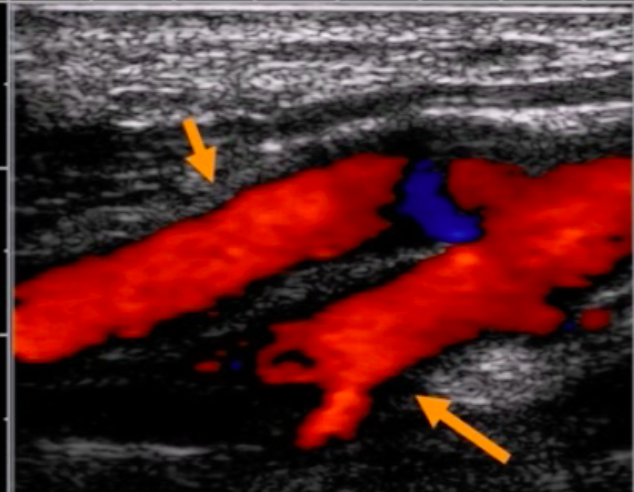

Identify the 2 vessels* in the images shown below.

*the vessels with arrows pointing to them

top vessel is ICA and bottom vessel is ECA

bottom vessel has branches ⇒ it is the ECA